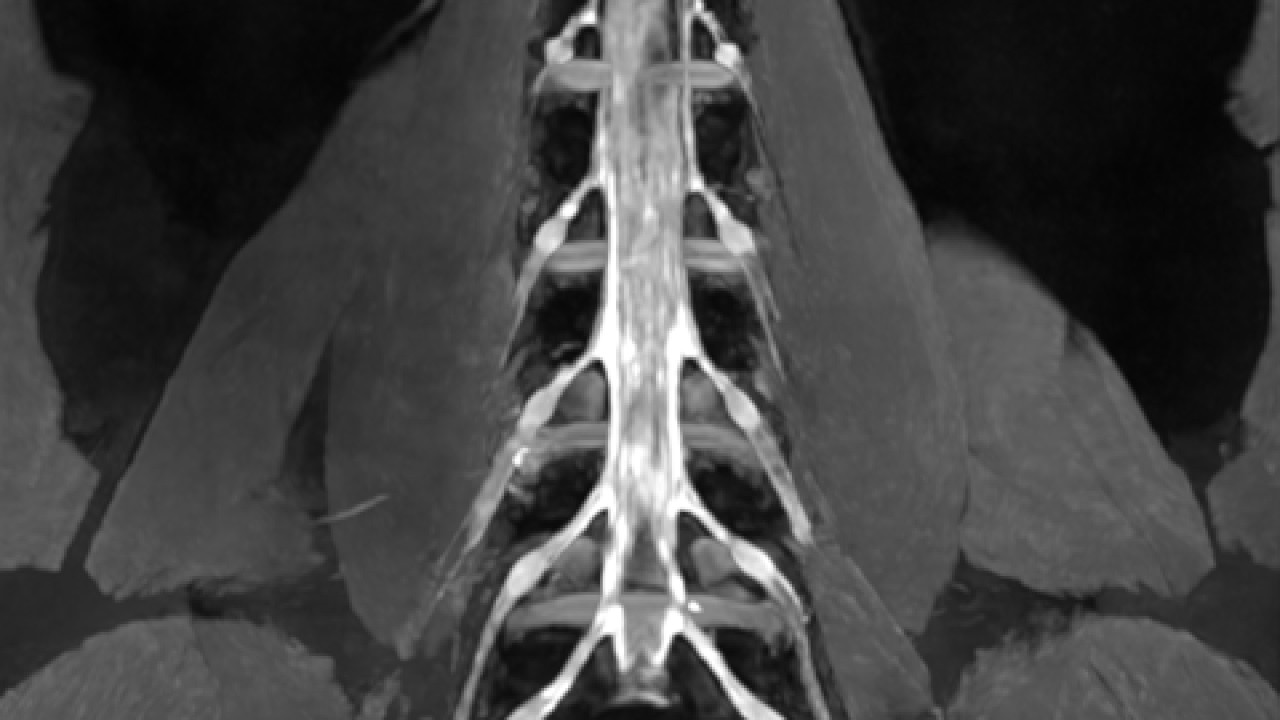

High-resolution lumbar plexus imaging. Image courtesy of United Imaging.